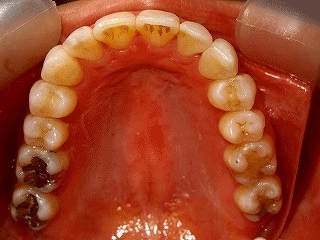

矯 正 前 後 の 口 腔 内 歯 列 観-2

矯 正前 上顎歯列観 矯 正後 上顎歯 列観